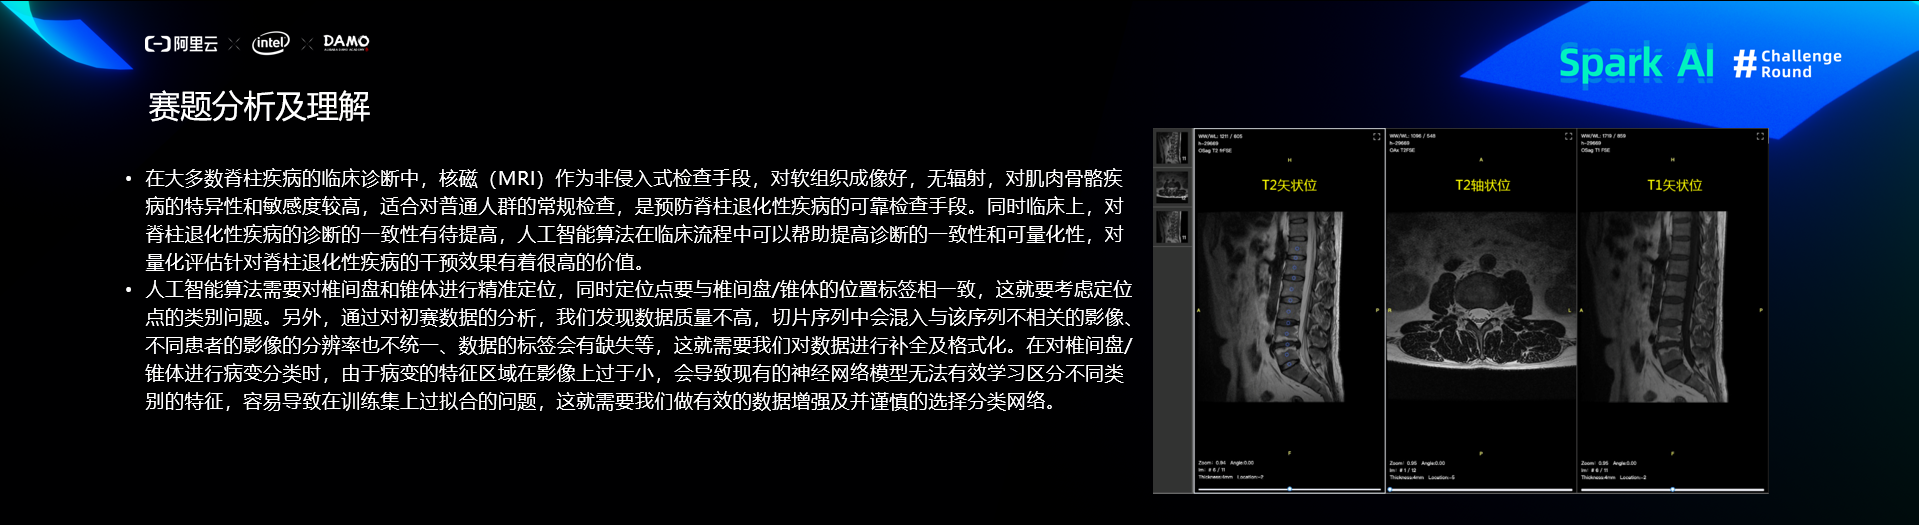

赛题分析及理解